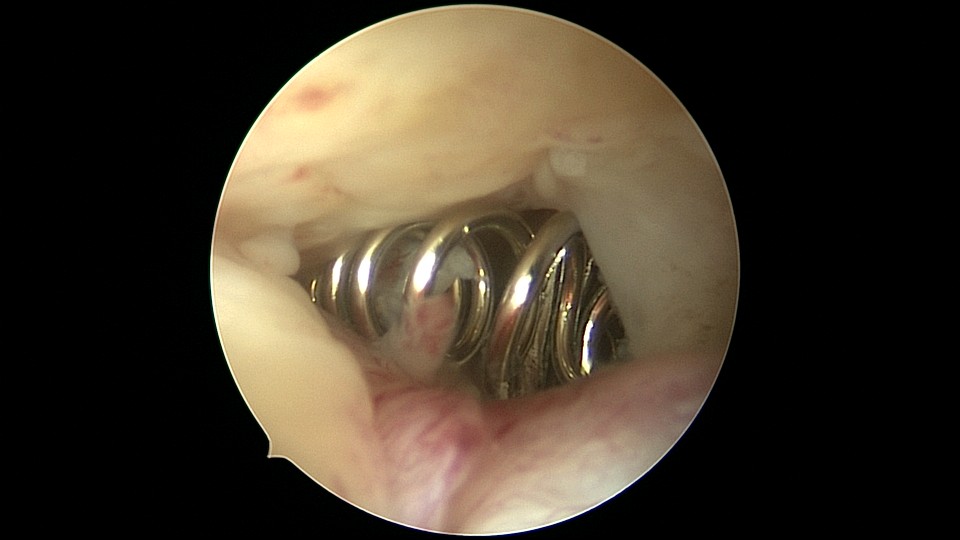

患者54岁,G1P1,剖宫产1次,安环30+年,绝经4年。40年前患者曾行左侧髋关节骨折手术,左下肢外展困难,患者肥胖,阴道很深,金属扩阴器和一次性扩阴器均无法暴露宫颈,用阴道内镜方式进入宫腔,但宫腔镜长度不够,远远能看见环,无法到达环的部位,再次试图暴露宫颈失败,用宫颈钳夹着阴道壁下拉,宫腔镜进入宫腔,但异物钳夹持力度不够,取出失败。用取环钩盲探沿宫腔镜外侧推挤进入宫腔,经历多次拧转,取环钩几乎向前弯成直角,直视下终于钩住节育环,掰直取环钩后缓慢拉出节育环,环变形。